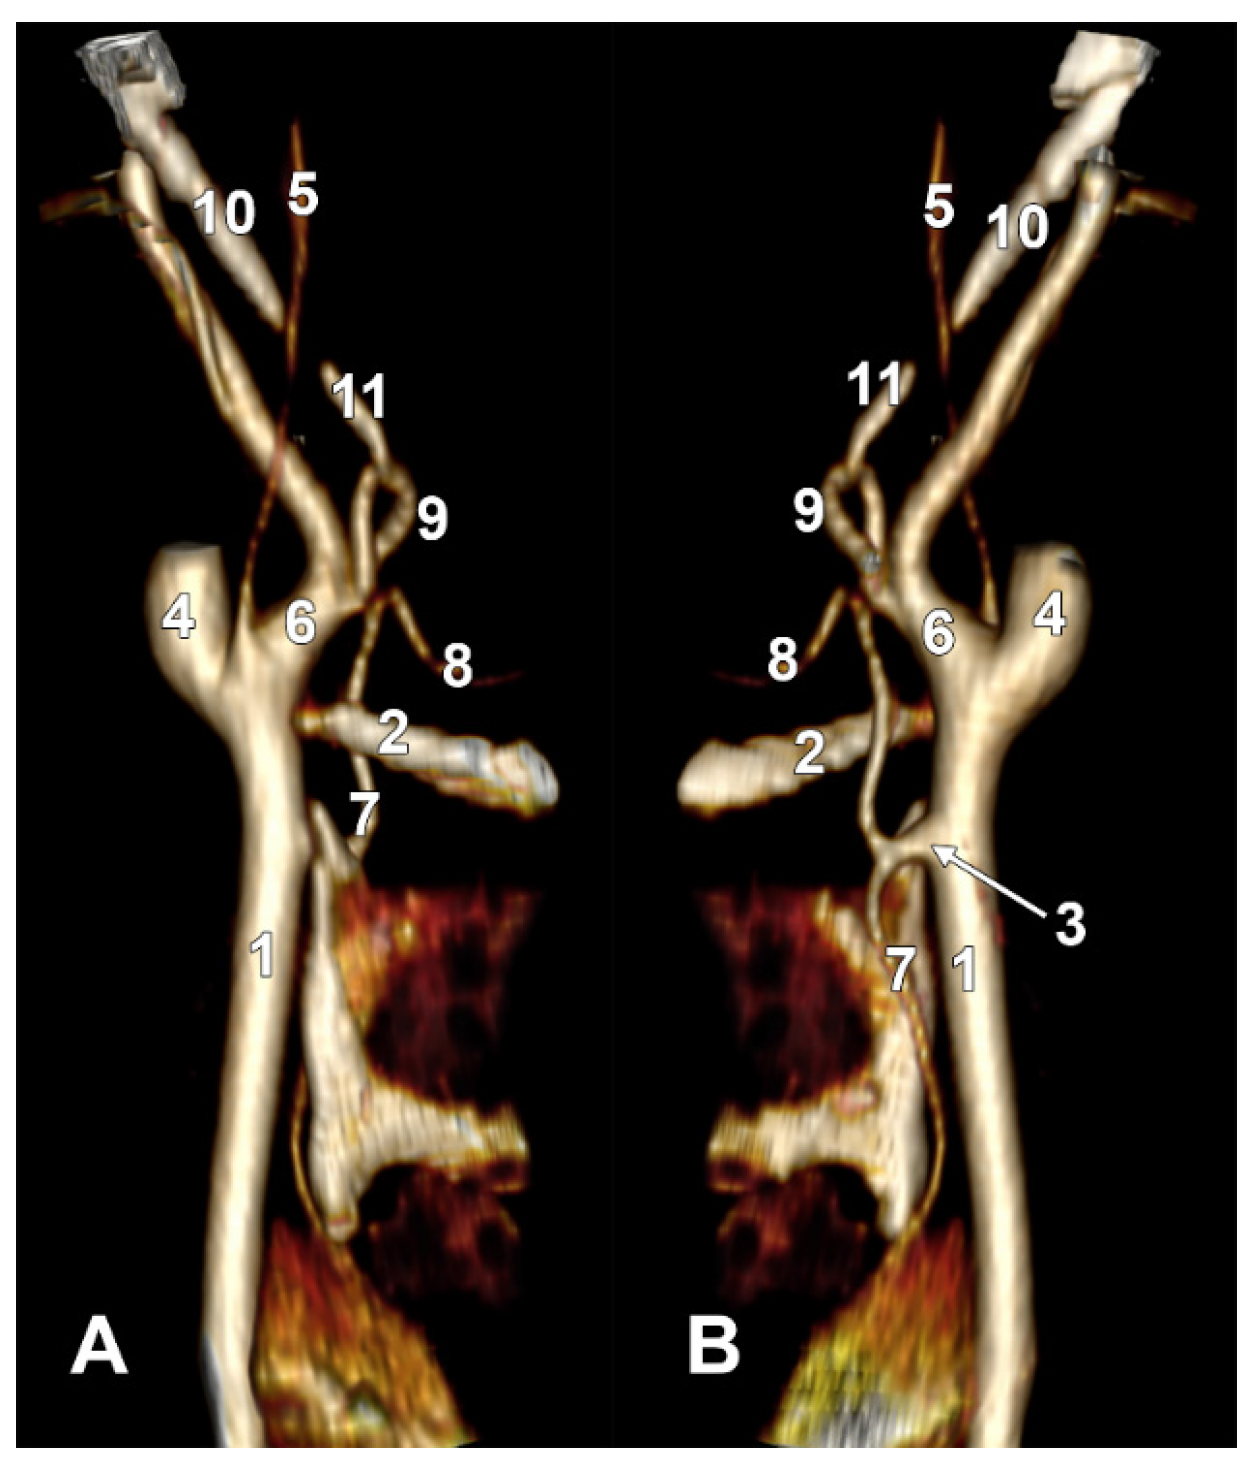

Figure 3. (A) Infrahyoid origin of the ascending pharyngeal artery. Linguofacial trunk. Three-dimensional rendering. Antero-infero-medial view. 1. Posterior auricular artery; 2. external carotid artery; 3. occipital artery; 4. internal carotid artery; 5. common carotid artery; 6. superior thyroid artery; 7. greater hyoid horn; 8. lingual artery; 9. facial artery; 10. ascending pharyngeal artery. (B) The hyoid origin of the ascending pharyngeal artery, lateral to the greater hyoid horn. Three-dimensional volume rendering. Right side. Posteromedial view. 1. Facial artery; 2. lingual artery; 3. greater hyoid horn; 4. superior thyroid artery; 5. common carotid artery; 6. internal carotid artery; 7. internal jugular vein; 8. ascending pharyngeal artery; 9. external carotid artery. (C) Occipitopharyngeal trunk and absent superior thyroid artery. Type S 37 of sequence of the origin of the external carotid branches. Three-dimensional rendering. Left side. Medial view. 1. Common carotid artery; 2. internal jugular vein; 3. internal carotid artery; 4. external carotid artery; 5. occipitopharyngeal trunk; 6. occipital artery; 7. ascending pharyngeal artery; 8. lingual artery; 9. facial artery; 10. hyoid tubercle.

3.3. The Hyoid Level of the APA’s Origin (Types SH/H/IH)

In the overall group of 170 sides, the APA originated inferior to the hyoid (IH type) in 8.24% of cases, at the hyoid level (H type) in 5.29% of cases, and suprahyoid (SH type) in 71.76% of cases, and was absent in the remaining sides. On the right side, the APA origin was infrahyoid in 8.24% (Figure 3A), hyoid in 7.06% (Figure 3B), and suprahyoid in 71.76% of cases, the rest being absent. On the left side, the APA origin was infrahyoid in 8.24%, hyoid in only 3.53% and suprahyoid in 71.76% of cases, the rest being absent.